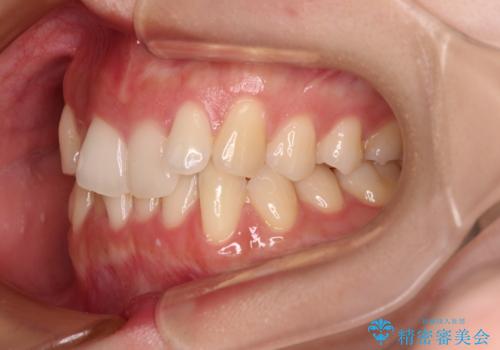

前歯が隠れるほどのデコボコをインビザライン矯正できれいに整える

マウスピース矯正特有の、奥歯が噛みにくくなるという現象の解消に少し期間をいただきましたが、日々の装着時間を遵守していただき、綺麗な歯列に整えることができました。